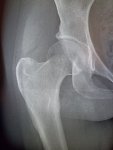

Здравствуй двачик, на прошлой неделе вышел из отпуска и уже дергается глазик, вчера сидел на работке пока поликлинику не закрыли и не все доделал. Не могу перестать кричать внутри головы! Потому мы с вами будем сегодня играть в доктора! Я буду вам показывать фоточки а вы угадывать пиздецомы! Што шпогнали! Найдите поломку!